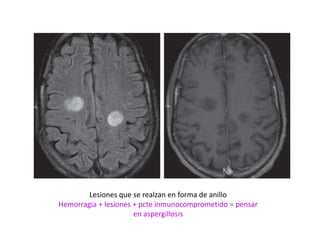

Lesiones que se realzan en forma de anillo

Hemorragia + lesiones + pcte inmunocomprometido = pensar

en aspergillosis

Lesiones que serealzan en forma de anillo Hemorragia + lesiones + pcte inmunocomprometido = pensar en aspergillosis